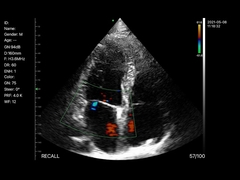

Wuxi Biomedical Technology Co., Ltd.

kualitas Portabel USG Scanner, Handheld Ultrasound Scanner manufacturer from China